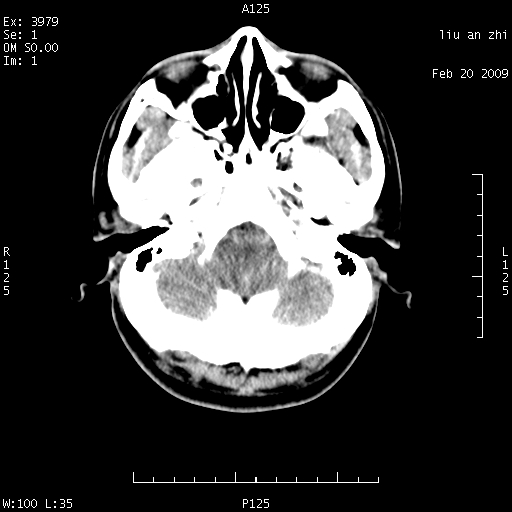

患者:男,32岁 被打伤后3天,自感头昏头痛作头颅ct检查。请大家看一下想什么??

请注意小脑幕!!!

考虑左侧天幕硬膜下血肿。

左侧天幕硬膜下血肿

左侧小脑幕旁硬膜下出血。